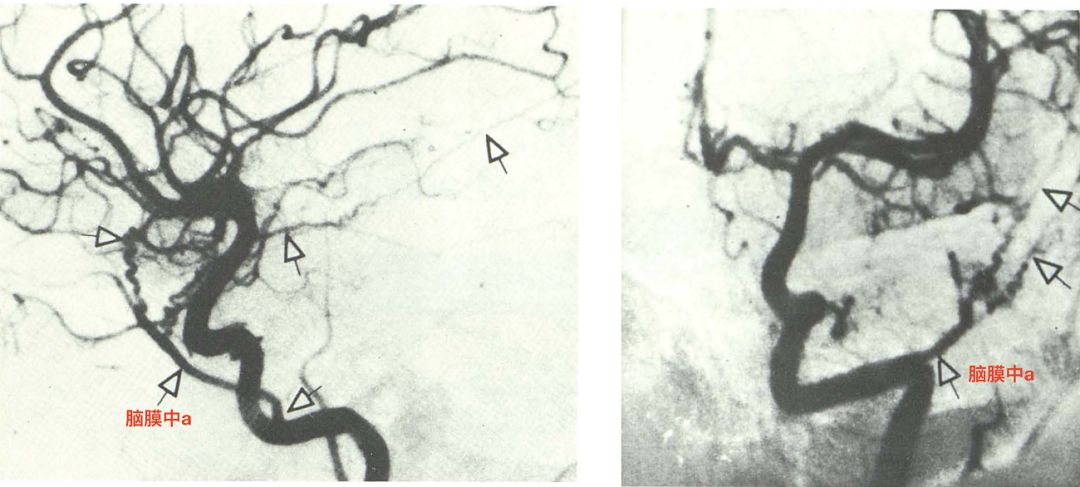

脑膜中动脉发自眼动脉(Dilenge 1980)。颈总动脉造影,可见脑膜中动脉发自眼动脉。未发自上颌内动脉。

Kimball等在一例因急性心肌梗塞而死亡的73岁女性尸检中,发现左侧脑膜中动脉发自眶上裂外侧(Kimball 2015)。脑膜中动脉发自眼动脉的外侧分支。同侧棘孔缺如。对侧棘孔存在。

眼动脉发自颈内动脉,并经过眶上裂入眶。分为内侧支和外侧支。内侧支供应眼球,脑膜中动脉和泪腺动脉发自其外侧支(Kimball 2015)。